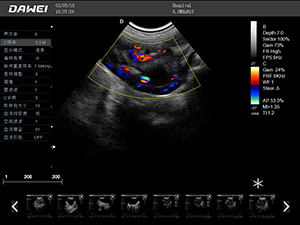

F5-VET彩色多普勒動物超聲診斷儀

F5-VET是一款性能可靠的獸用全數字彩色多普勒超聲診斷系統,基于Windows平臺 配置固態盤快速啟動 穩定可靠,融合了全面豐富的臨床應用,結合優異的人機工程學設計,推動了臨床診斷新趨勢。

·探頭接口:≥4個 可配備凸陣、微凸陣、線陣、相控陣、經直腸等各類獸用專用探頭,并配有犬、貓、馬等動物的專用測量軟件,是一款應用全面的獸用彩超。

·中小動物的肝、膽,脾、腎、膀胱、子宮、妊娠等各組織器官的檢查和病變的診斷